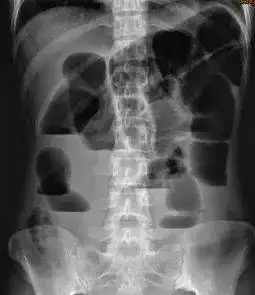

患者郭某,中年女性,于今年5月25日车祸受伤,伤及左下肢及左骶尾部

盆腔dr正位片示膀胱结石.